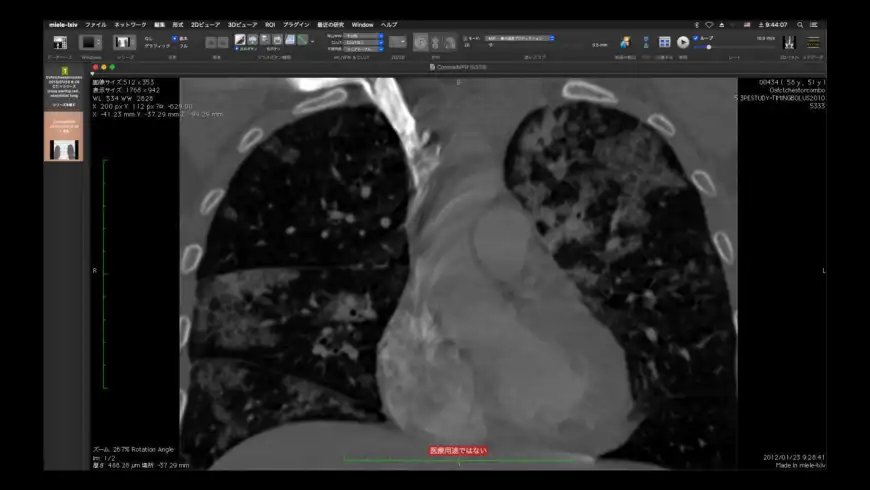

DICOM workstation and viewer.

Miele-LXIV overview

Miele-LXIV is a DICOM workstation, viewer and more.

Miele-LXIV is a DICOM workstation, viewer and more.